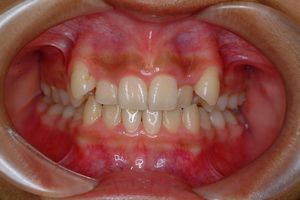

健康な小臼歯を抜いていません

矯正前                 矯正後

治療前 の 正面 です 動く矢印治療後 の 正面 です